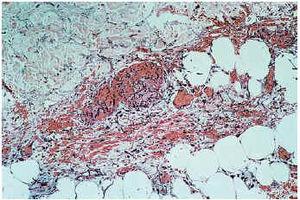

Se realizó biopsia de una de las lesiones y toma de muestra para cultivo microbiológico. El estudio histológico, confirmado con PAS, demostró la presencia de hifas tabicadas y ramificadas localizadas por toda la dermis e hipodermis con invasión masiva de los vasos (figs. 2 y 3). El cultivo microbiológico fue positivo para Aspergillus niger.

Fig. 3.--Confirmación de las estructuras micelares mediante la tinción con PAS (×20).

En el estudio histológico de las lesiones cutáneas con la tinción de ácido periódico de Schif (PAS) o con metamina-plata se observan hifas tabicadas, ramificadas en ángulo agudo y con tendencia a la invasión y trombosis de los vasos, que es muy orientativa de infección por Aspergillus sp.; no obstante, hay que hacer el diagnóstico diferencial con otras micosis de la especie Fusarium sp. y Pseudallescheria boydii, por lo que el diagnóstico de confirmación se obtiene con el crecimiento del hongo en medio de Saboraud4, 17.